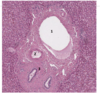

In the image below what does number 1 depict?

- lumen of the GIT

In the image below what does number 2 depict in the 4 layers that is present in the GIT?

- mucosa

- epithelium + lamina propria = mucosa

In the image below what does number 3 depict in the 4 layers that is present in the GIT?

- submucosa

In the image below what does number 4 depict in the 4 layers that is present in the GIT?

- muscularis propria

In the image below what does number 5 depict in the 4 layers that is present in the GIT?

- serous